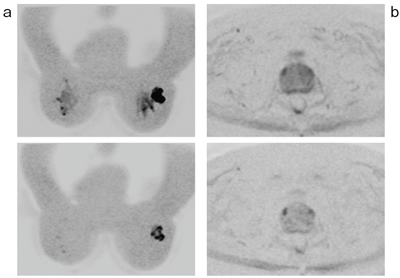

IDEAL-IQ開発の基礎技術となった3-point Dixon法の“IDEAL”,および2-point Dixon法の“FLEX”は,得られた信号から局所的な磁場不均一を算出(フィールドマップ計算)し,この情報を画像再構成の位相補正に用いることで,水・脂肪信号の分離を行っている。IDEALおよびFLEXのいずれにおいても,水・脂肪の分離を行っているが,肝臓領域において,ボクセル内の脂肪含有率(fat fraction)マッピングを正確に計算するには,もうひと工夫が必要である。これは肝臓内の生理的な鉄沈着によるT2*減衰の影響が無視できないためである。さらに,生体内の脂肪は,メインピークとは別の幾つかのケミカルシフトを有しており,これらも考慮する必要がある。そこで,新たに開発されたIDEAL-IQでは,6つ以上の異なるTEからエコー信号を受信し,増えた情報量からT2*の計算,ならびにマルチピークの脂肪量を計算する。これにより,1回の息止め撮像でIDEAL同様の水・脂肪の分離画像,さらにはボクセル内のR2*(T2*の逆数)マッピング,脂肪含有率マッピングを得ることができる(図6)。撮像は3Dでの撮像で,実際に作成したマッピング例を図7に示す。左は脂肪肝,右は正常肝の例であり,ROIを計測すると,明らかに異なる値が表示されている。

![]() 図6 IDEAL-IQの原理概念図 |

![]() 図7 IDEAL-IQの脂肪含有率マッピング例 a:fat fraction=31%(脂肪肝) b:fat fraction=2%(正常肝) |